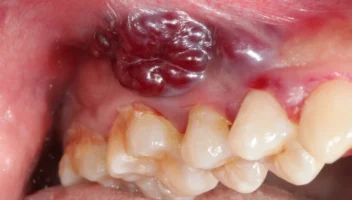

Oral Melanoma: A Rare but Aggressive Malignancy of the Mouth

Melanoma is most commonly associated with skin cancer, where it originates from melanocytes, the pigment-producing cells in the skin. However, melanocytes are also present in other parts of the body, including mucous membranes. When melanoma arises from these mucous membranes, it is termed mucosal melanoma. Oral melanoma, a subtype of mucosal melanoma, originates in the […]